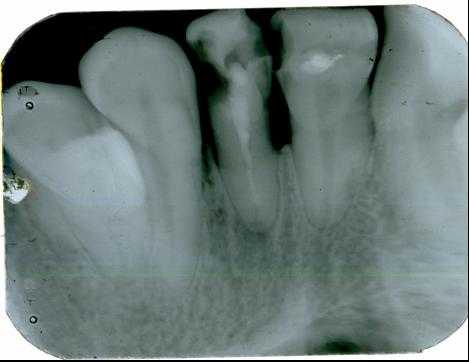

Основой рентгенологического исследования при большинстве заболеваний зубов и пародонта по-прежнему служит внутриротовая рентгенография.

На одном снимке можно получить изображение не более 2-3 зубов

Прямые панорамные рентгенограммы имеют преимущество перед внутриротовыми снимками по богатству деталями изображения костной ткани и твердых тканей зубов. При минимальной лучевой нагрузке они позволяют получить широкий обзор альвеолярного отростка и зубного ряда, облегчают работу рентгенолаборанта и резко сокращают время исследования. На этих снимках хорошо видны полости зуба, корневые каналы, периодонтальные щели, межальвеолярные гребни и костная структура не только альвеолярных отростков, но и тел челюстей. На панорамных рентгенограммах выявляются альвеолярная бухта и нижняя стенка верхнечелюстной пазухи, нижнечелюстной канал и основание нижнечелюстной кости.

На основании панорамных снимков диагностируют кариес и его осложнения, кисты разных типов, новообразования, повреждения челюстных костей и зубов, воспалительные и системные поражения. У детей хорошо определяется состояние и положение зачатков зубов.